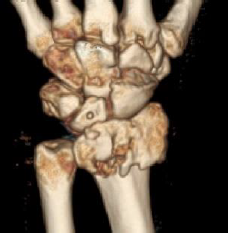

손목 골절의 대표 유형

- 분쇄·불안정 골절

- 고에너지 충격(추락·교통사고)에서 발생, 골편이 여러 조각.

- 수술적 고정(금속판·나사) 후 재활 필요.